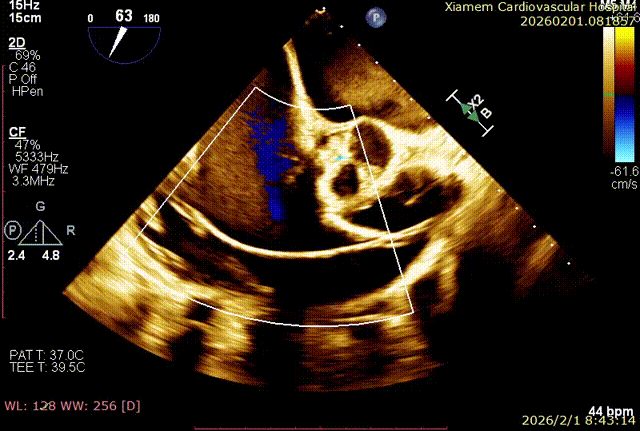

T-TEER 手术过程术前 TTE+TEE 评估:全心扩大,右房横径 8.3cm,左房横径 5.2cm;三尖瓣房性功能性反流,Type ⅢB 型(后叶为两瓣),反流程度 4+(Massive),缩流颈宽度 VC 为 14.5mm;TAPSE 为 1.3cm, LVEF(%)为 72%。

第一个夹子释放后,在前叶、隔叶间靠近中央区仍有残余反流,所以决定再植入一枚 6mm 夹合器。第二枚夹合器抓捕瓣叶过程中,受到第一枚夹合器影响,无法清晰的在 X-plane 切面上进行瓣叶捕获,因此改用 3D-MultiView 切面顺利抓捕,关闭夹合器后残余反流已经由术前极重度(4+)减小为轻中度(2+),手术过程流畅,手术结果完美。

术后即刻反流改善为2+